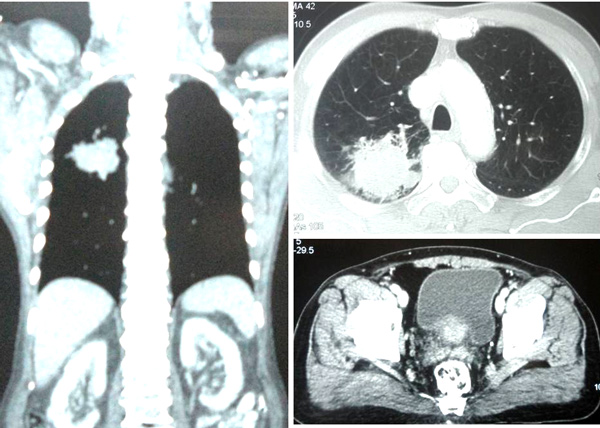

A CT scan on 30 October 2013 showed:

- Sclerotic lesions at vertebral bodies of L3, L4 and L5 – likely metastases.

From April 2014 to December 2014 Jack also received 6 to 8 monthly injections of Denosumab. This is a monoclonal antibody used to treat bone cancer. It is also known by its brand name, Xgeva and Prolia.